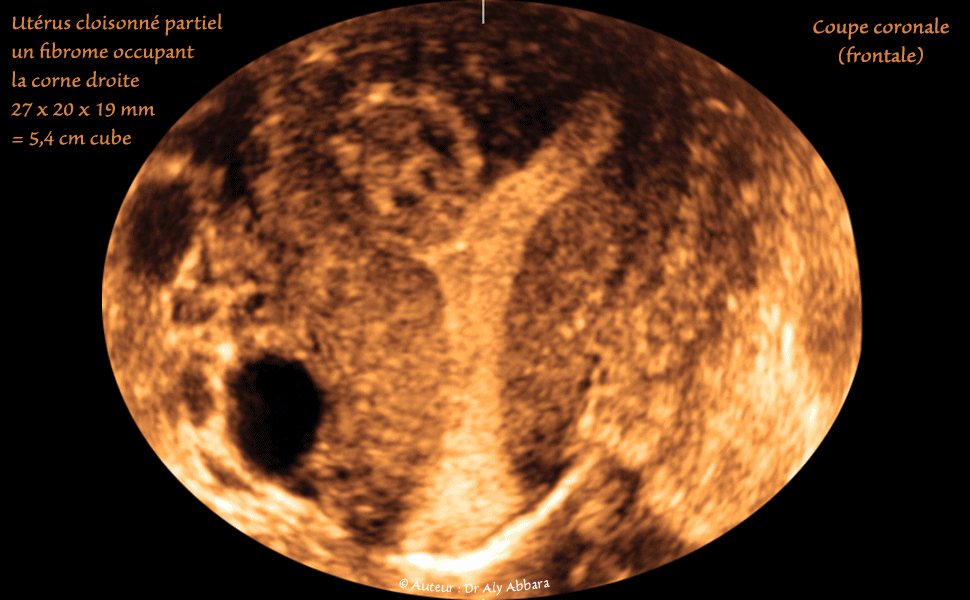

• Images échographiques montrant (sur des coupes sagittale, transverse et frontale) un utérus malformé, cloisonné corporéal partiel : cloison partiellement divisant la cavité du corps utérin en deux compartiments, droit et gauche.

Le compartiment droit de la cavité utérine fundique contient une masse ovale de 27 x 20 x 19 mm de diamètre, soit 5,4 cm3 de volume, il s'agit d'un vieux myome asymptomatique partiellement calcifié (histologiquement confirmé), sous muqueux (classe 0 selon le FIGO).